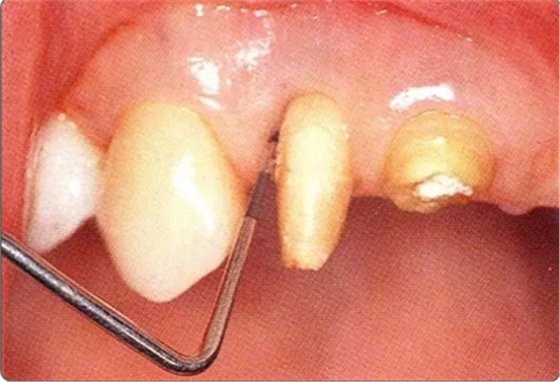

圖10-1

遠(yuǎn)中部有8mm的牙周袋。上頜前牙部等需要考慮審美性的部位進(jìn)行GTR法,但也可能會(huì)出現(xiàn)齦瓣壞死導(dǎo)致牙齦乳頭喪失,反而導(dǎo)致審美性變差的情況。